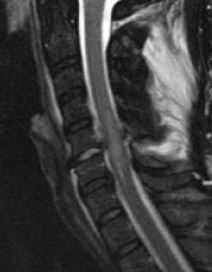

МРТ позвоночника. Т2-взвешенная сагиттальная МРТ. Компрессия спинного мозга. Цветовая обработка изображения.

Изменение клинической симтоматики в хроническом периоде травмы, такое как наростание симптомов миелопатиии, повышение уровня неврологического дефицита, боли и увеличение мышечного спазма служат признаками развития поздних осложнений. Для оценки их характера показана МРТ позвоночника. Вместе с тем, надо иметь ввиду, что у таких пациентов часто имплантированы металлические конструкции, создающие артефакты. Осторожности требует исследование пациентов с нейростимуляторами.

Типичными для хронической травмы изменениями при МРТ позвоночника являются миеломаляция, киста и атрофия спинного мозга. Посттравматический отёк спинного мозга приводит к его ишемии, с последующей демиелинизаций и глиозом. Патогенетической основой формирования кисты служит интрамедуллярная гематома. При ее резорбции остаётся локальная киста. Соединение кисты со спинномозговым каналом приводит к его расширению, а адгезия к нарушению оттока ликвора.